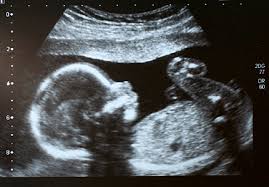

Pregnancy is a very personal topic to myself as i am currently pregnant. There are three types of scans given through-out a womans pregnancy originally two but a new growth scan has been recently introduced to take place during the early stages of the third trimester. In the first trimester a first scan is given and checks for a heart beat and checks on the current state of the baby, i,e if feet, hands, eyes important organs are functioning correctly, also a down syndrome test is taking. In the 2nd trimester a second scan is given this can tell the sex of the baby and also a check to see if there is any abdormalities.